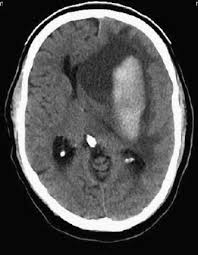

3. C is the correct answer. This patient has a large left sided subarachnoid hemorrhage with a midline shift. She needs her Coumadin reversed as soon as possible. Protamine is the reversal agent for heparin not Coumadin. Patients with subdural hematoma have the bleeding around the outside of the brain not in the parachemyma. This patient does not have a visible brain mass on CT scan. It is not uncommon for patients to bleed into the mass but they are usually more circumscribed and not so irregular.

3. Your patient is a 83 year old female who presents with a headache and the CT scan below. She is also on Coumadin. Based upon this data, which of the following is the best management plan?